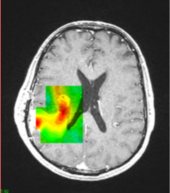

Unsere Gruppe widmet sich der angewandten Forschung in den Bereichen Physik der bildgebenden Verfahren in der Radiologie, sowie der Bildverarbeitung, der chirurgischen Navigation und der Dosimetrie von Röntgenstrahlung. Der Schwerpunkt liegt auf digitalen Bildgebungsmodalitäten (DR und CR), CT und Ultraschall.

Wir unterstützen die Optimierung der Patientenversorgung durch technische Innovation, Forschung und Ausbildung von Studierenden der Medizin, Physik und BMT und RTs (Studierenden und KollegInnen). Wir beschäftigen uns auch mit der Weiterbildung von ÄrztInnen, und unterstützen bei der Optimierung bei diagnostischen und interventionellen radiologischen Verfahren. Wir beraten klinische KollegInnen des AKH Wien bei Fragen der klinischen Medizinphysik.